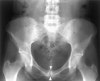

OA 소견(연골하낭종, 미란, 경화, 골극 등)이 있으며, 치골결합의 폭이 7mm 이상이거나 상하로 2mm의 이동이 있을 때 불안정성이 있습니다.

X-ray : 치골골염(Osteitis pubis)